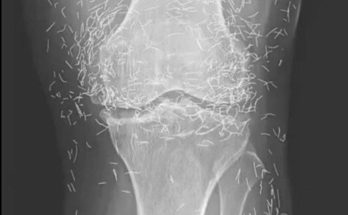

When a 65-year-old woman in South Korea went to the doctor because of worsening knee pain, no one expected the scans to reveal anything unusual. The visit was supposed to …